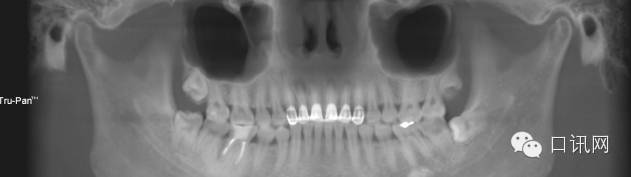

X片显示:11,12,13,21,22,23根充物欠填4-5mm口腔临床执业医师12根尖阴影大 约3.3*5.5mm口腔医学技术11,13,21,22根尖有阴影口腔修复工艺

术前全景片